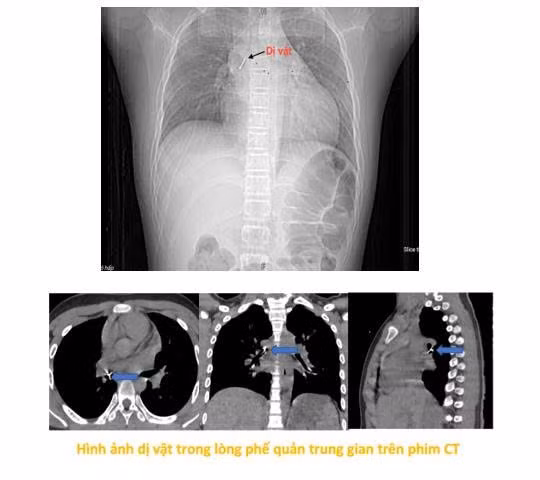

Tại đây, bệnh nhi được làm các xét nghiệm máu, chụp phim cắt lớp vi tính lồng ngực, nội soi phế quản ống mềm, các bác sĩ xác định dị vật đã nằm sâu trong phế quản trung gian bên phải.

“Dị vật là chiếc đinh ghim sắc nhọn, nằm vướng tại phế quản trung gian, đầu nhọn đâm xuyên sâu vào thành phế quản. Đây là ca gắp dị vật rất khó, bởi ngoài tính chất, đặc điểm của dị vật như trên, bệnh nhi còn phản ứng theo phản xạ nên cần đòi hỏi thao tác nhanh, chính xác tuyệt đối để tránh làm rách thành phế quản hay đẩy dị vật xuống sâu hơn, có thể dẫn tới nhiễm trùng, chảy máu, tràn khí màng phổi, tràn khí trung thất. Thậm chí những biến chứng đó có thể gây hậu quả suy hô hấp cấp cho người bệnh.